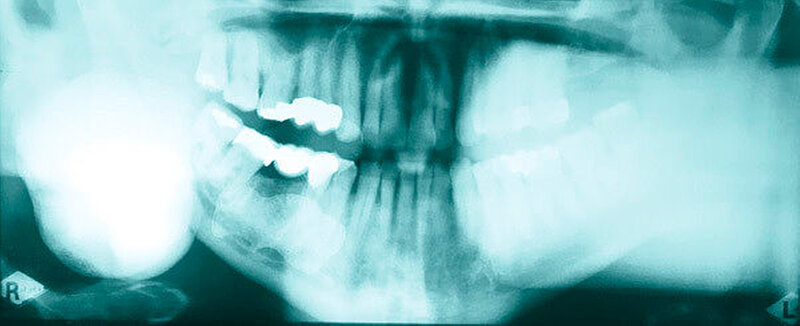

Im mitgebrachten alio loco erstellten Orthopantomogramm war eine gut abgrenzbare, ovale, homogene Verschattung zu sehen, welche sich im Bereich des rechten Kieferwinkels, in dorsaler und kranialer Richtung über diesen hinaus sowie im Bereich des aufsteigenden Unterkieferastes bis kaudal unter die Incisura semilunaris erstreckte (Abbildung 1). Computertomografisch war ausgehend von der medialseitigen Corticalis des Angulus mandibulae rechts eine irregulär, angedeutet rundlich konfigurierte, glatt begrenzte knöcherne Raumforderung von circa 4,4 x 3,3 x 4,7 cm Größe zu sehen (Abbildungen 2 und 3). Diese führte zu einer Verlagerung der Anatomie, insbesondere zu einer Vorwölbung der rechtsseitigen Oropharynxseitenwand (Abbildung 4). Es bestanden keine Hinweise auf eine knöcherne Destruktion oder auf eine Lagebeziehung zu einem Zahn.